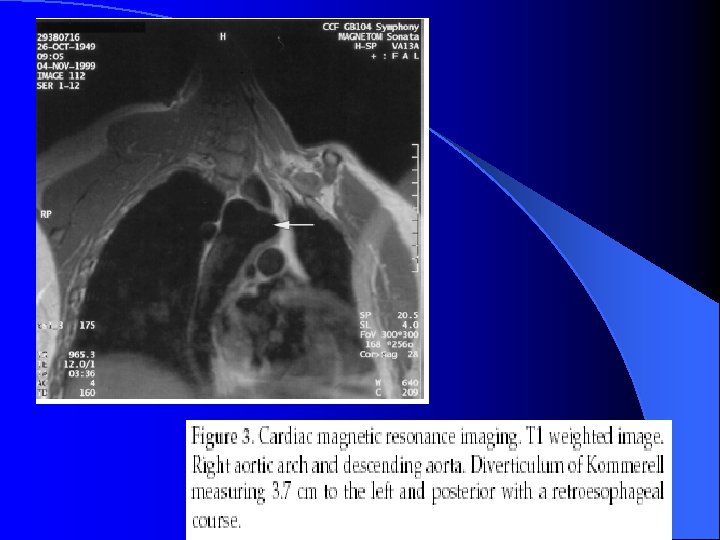

Dysphagia Lusoria “Dysphagia of unclear etiology” l Congenital anomalies of aortic arch: l – Double aortic arch – Anomalous origin of R or L subclavian artery – Kommerell’s Diverticulum – saccular aneurysmal dilation at of ARSA or ALSA – If LA or ductus present between subclavian and pulmonary complete vascular tracheobronchial ring l Presents as respiratory distress, dysphagia & stridor

Dysphagia Lusoria l Dx: – CXR – Barium swallow w/ esophogram l Tx: – Sx repair through lateral thoracotomy with lung separation